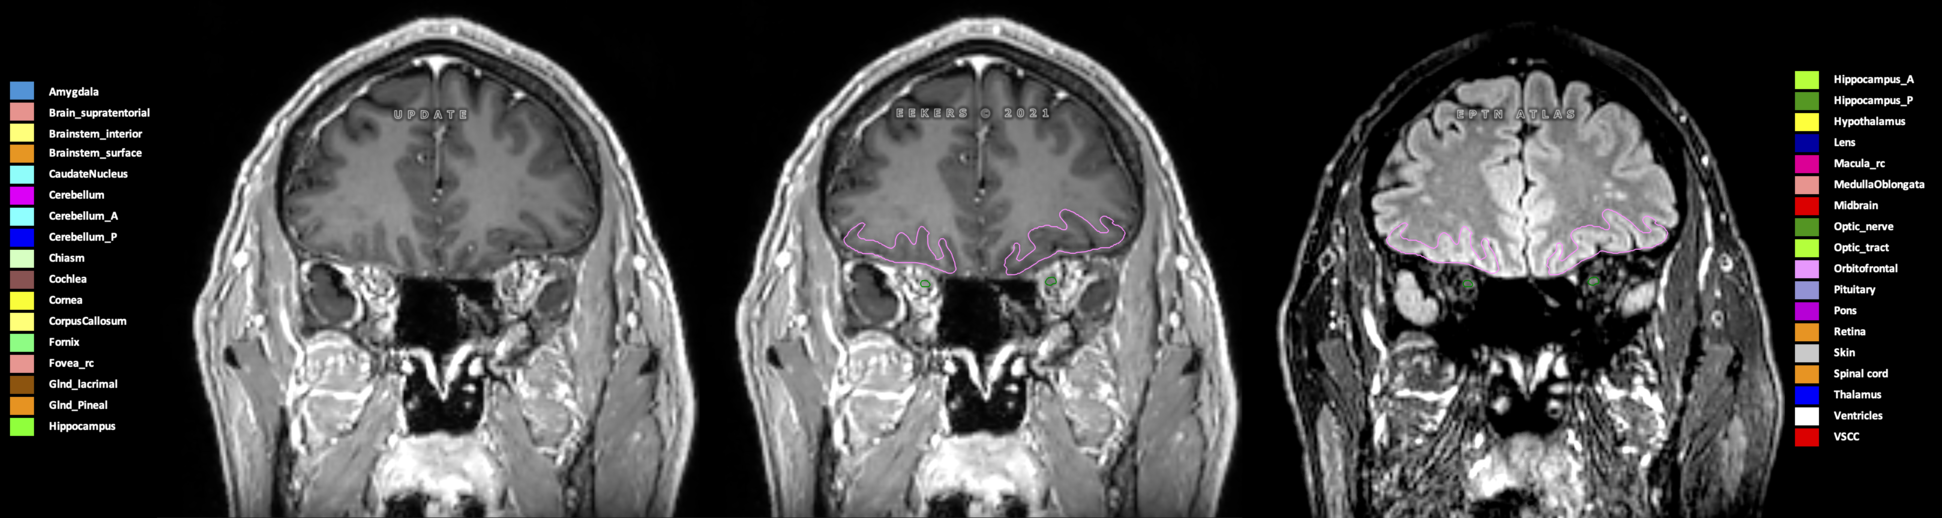

Eekers et al. have published an international neurological atlas for contouring of organs at risk in consensus with the European Particle Therapy Network (EPTN) in 2018 and an update in 2021. The purpose of this consensus atlas is to decrease inter- and intra-observer variability in delineating OARs relevant for neuro-oncology.

Included are all OARs known to be relevant for radiation-induced toxicity in neuro-oncology: brain, brainstem (midbrain, pons, medulla oblongata), chiasm, cerebellum (anterior & posterior), cochlea, cornea, hippocampus (anterior & posterior), hypothalamus, lens, lacrimal gland, optic nerve, pituitary, skin, and vestibular & semicircular canals. To further facilitate research on cognition, vision and radiological changes after irradiation of the brain, potential clinically-relevant OARs are included: amygdala, caudate nucleus, cerebellum (anterior & posterior), corpus callosum, fornix, macula, optic tract, orbitofrontal cortex, periventricular space (PVS), pineal gland, and thalamus.

Three-dimensional delineation of the 25 consensus OARs for neuro-oncology are shown on CT (WW/WL 120/40, 3000/600), 3T MR images, (T1Gd, T2FLAIR 1mm) and 7T MR (MP2RAGE 0.7 mm). All are presented in transversal, sagittal and coronal view.